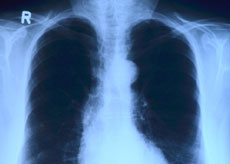

● 결핵검사

흉부 X-ray 촬영을 통해 폐결핵 여부를 확인합니다. 검사 시 귀걸이, 목걸이 등의 액세서리와 속옷을 벗고 가운을 착용해야 합니다.